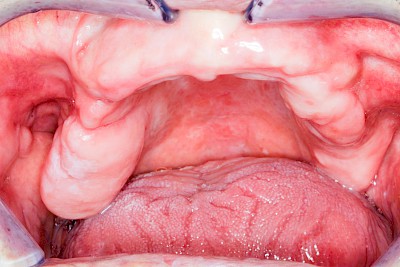

Überbein (Exostose)

Überbeine im Bereich der Kiefer sind gar nicht so selten. Häufiger im Bereich der Seitenzähne unterhalb des Zahnfleisches, aber auch in der Mitte vom Gaumen. Überbeine haben in dem Sinne keinen Krankheitswert, müssen also nicht operativ entfernt werden, wenn diese nicht stören. Überbeine können ein Anzeichen für Knirschen und Pressen sein.